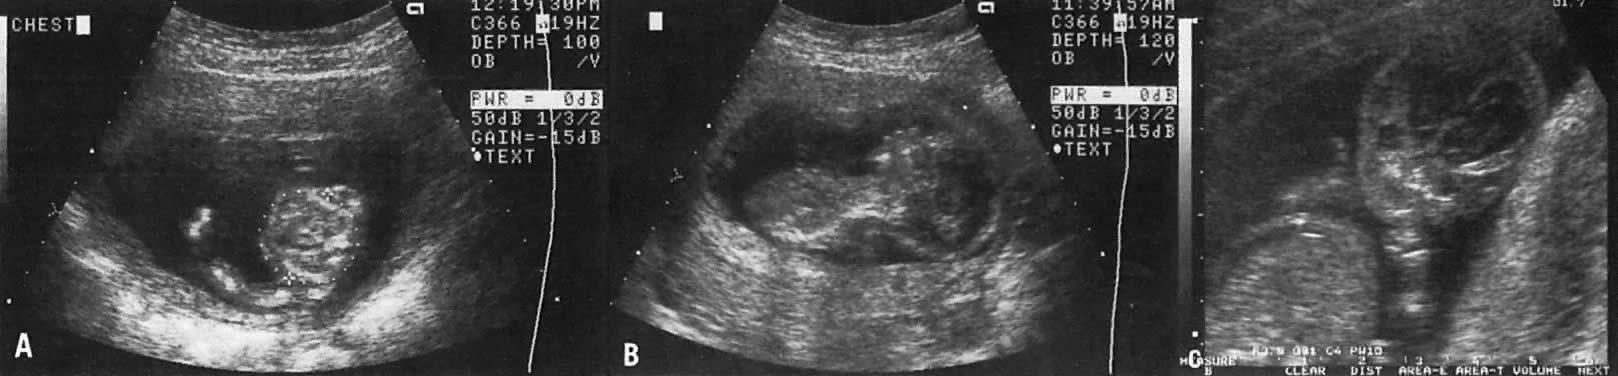

The etiology of a dilated renal pelvis or pyelectasis is similar to that of a dilated UPJ. Reflux occurring at the level of the vesicoureteral valves also may result in pyelectasis (Fig. 15).

Fig. 15. Echogram showing a cross-section of the fetal abdomen at the level of the kidneys. The spine is anterior. Note bilateral pyelectasis (calipers). The anteroposterior diameter of each renal pelvis measure 5 mm.

The definition of mild or minimal pyelectasis in the literature is confusing.47 Further, the outcome of fetuses with minimal pyelectasis is not all “benign” as suggested in some studies.48 In fact, many such fetuses may require subsequent medical or surgical intervention. Thus, an anteroposterior diameter equal to or greater than 4 mm or 7 mm before and after 33 weeks' gestation, respectively, warrants postnatal follow-up.48

Moreover., approximately 3.3% of fetuses with pyelectasis in the range of 3 to 5 mm may also have chromosomal abnormalities, including Down syndrome.49, 50 Interestingly, 25% of fetuses with Down syndrome have pyelectasis, whereas only 2.8% of fetuses with a normal karyotype show this condition.49